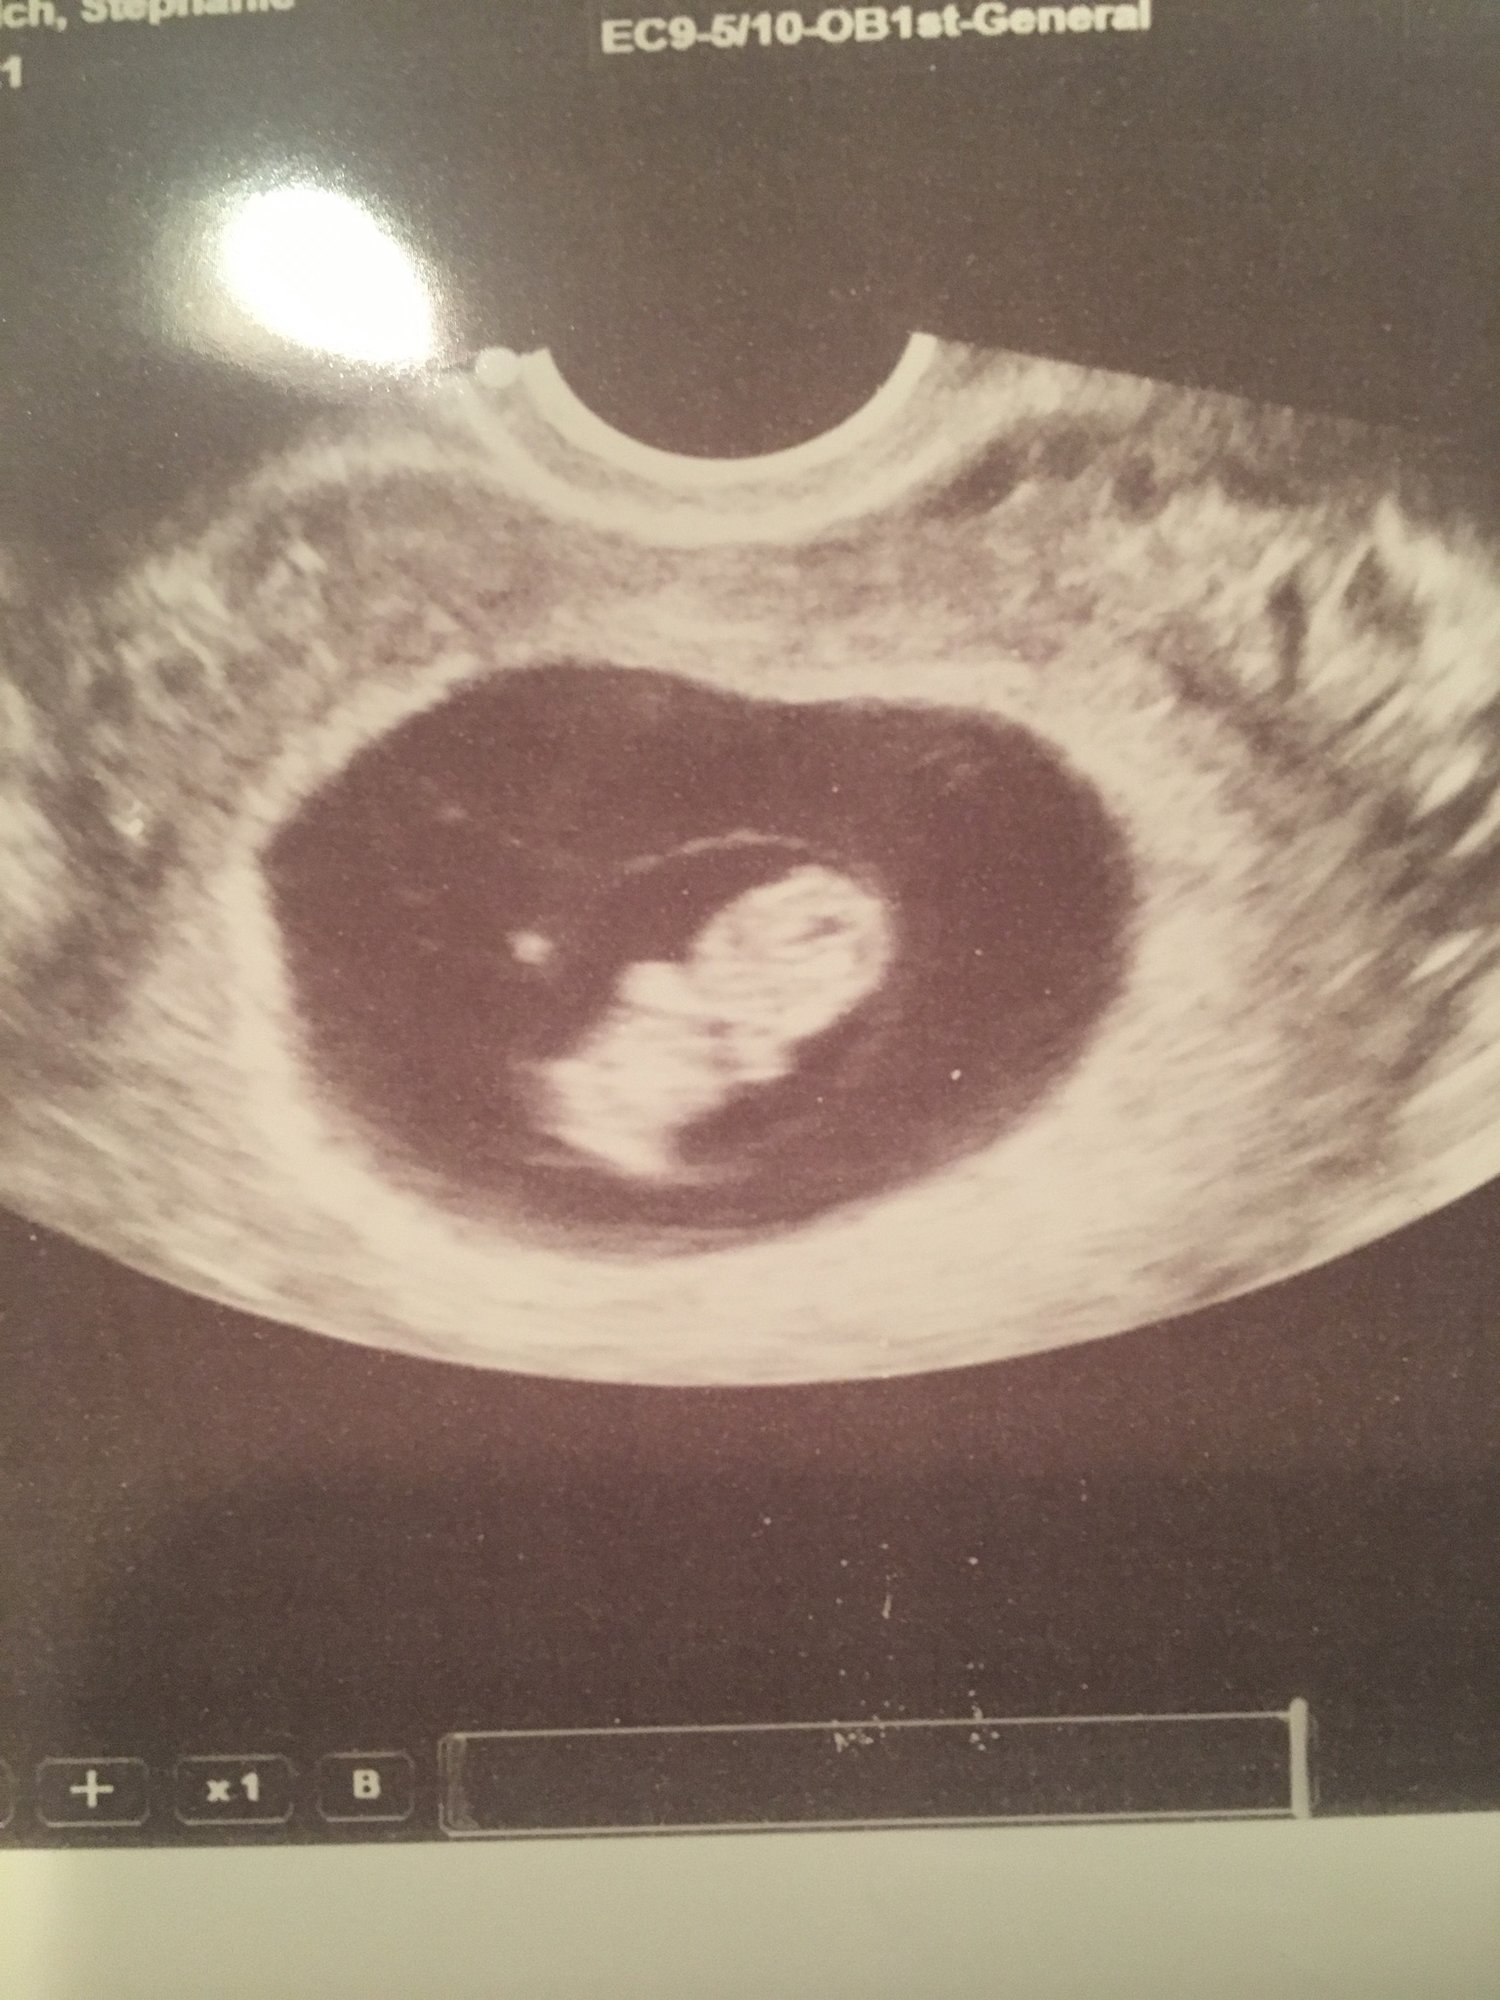

Hi ladies, had another ultrasound today and wow what growth from last week! I measuring a day behind. Hope you don’t mind the share- still shocked there’s a real baby in there! The only concerning thing was she mentioned I had some “laking”- that’s a phonetic spelling because I can’t figure out the right spelling for the term as I googled it. It has something to do with the blood vessels. She says no exercise, lots of rest and “they won’t put me on bed rest unless it worsens.” I’m sorry what now? Ain’t no one got time for bed rest at this stage. It was the sonographer I don’t trust and seems to know nothing so I didn’t even bother to ask additional questions. Anyone know about this?

• Looks good @lablover78! Like a real baby

• @lablover Do you think they maybe mean it is like a blood clot or SHM as some call it? Some women don't see any bleeding from it but it's just a little bleeding outside of sac and baby in uterus.  They say it will resolve itself.

Also I was just wondering today if anyone on here will share their Sonos. I'm glad you did!

• @lablover78 that is quite the little cutie you have there I can see its little arms and legs!  Thank you for sharing your pic.  We only have a printed one but I bet I can take a picture with my phone and share it with you guys!  I have no idea what laking can be.  I would call the clinic to get clarification.  It’s so hard to in the moment get more information and with the fear of bed rest I would want to know what’s going on!  Hoping its nothing.  They told me I had blood on my ultrasound but didn’t give me any restrictions, and I never ended up bleeding.  No idea where it went because it didn’t come out.  So hopefully it’s just something like that.

• Aw thanks ladies!! I think you ladies are right about the SCH because she did stress NO exercise and have been telling me know sex/orgasm the whole time. @2MomsHoping❤️ Yes arms & legs unbelievable- yes please share your pic